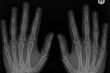

Coraz częściej wszczepiane pacjentom metalowe implanty zastępują nowoczesne polimery. Prace badawcze nad polimerami bioresorbowalnymi rozpoczyna także białostocka spółka ChM.